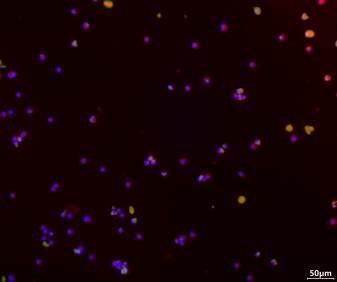

Immunofluorescence results show that the drug can significantly enhance macrophage M2 polarization and inhibit M1 polarization.